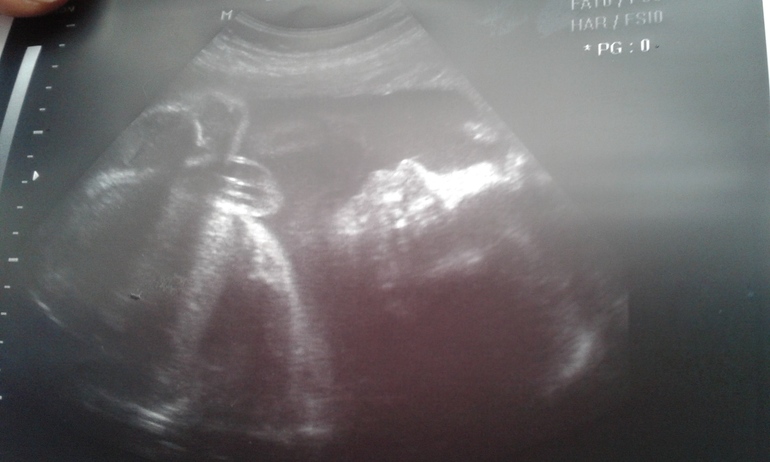

Вот и съездили мы с дочей на узи (видимо последнее за эту беременность). Идет нам 30 неделька и врач отправила меня посмотреть, как там моя малышка поживает

Врач встретила меня приветливо! Передо мной был большой телевизор и я могла наблюдать мою малышку всю процедуру узи. Врач (Полякова, очень понравилась, думаю еще к ней пойду если что) - все подробно показывала и рассказывала: мозг со всеми отделами, костную систему, все внутренние органы (сердце, легкие, желудок и пр..), включила сердечко (140 ударов в минуту).

Вот, что получилось:

1. Располагаемся головкой вниз, продольно

2. Весим 1330 г

3. ЧСС- 140 ударов в минуту

4. Плацента по передней левой стенке, 1 стадия зрелости

5. Прирост плода - адекватный и признаков гипоксии и пороки - не обнаружены

Заключение: соответствуем полным 29 неделям )))

Узистка пыталась еще показать мне мою масю в 3д, но она закрылась ручками, так личико не удалось увидеть((( Зато дали фотки в 2д